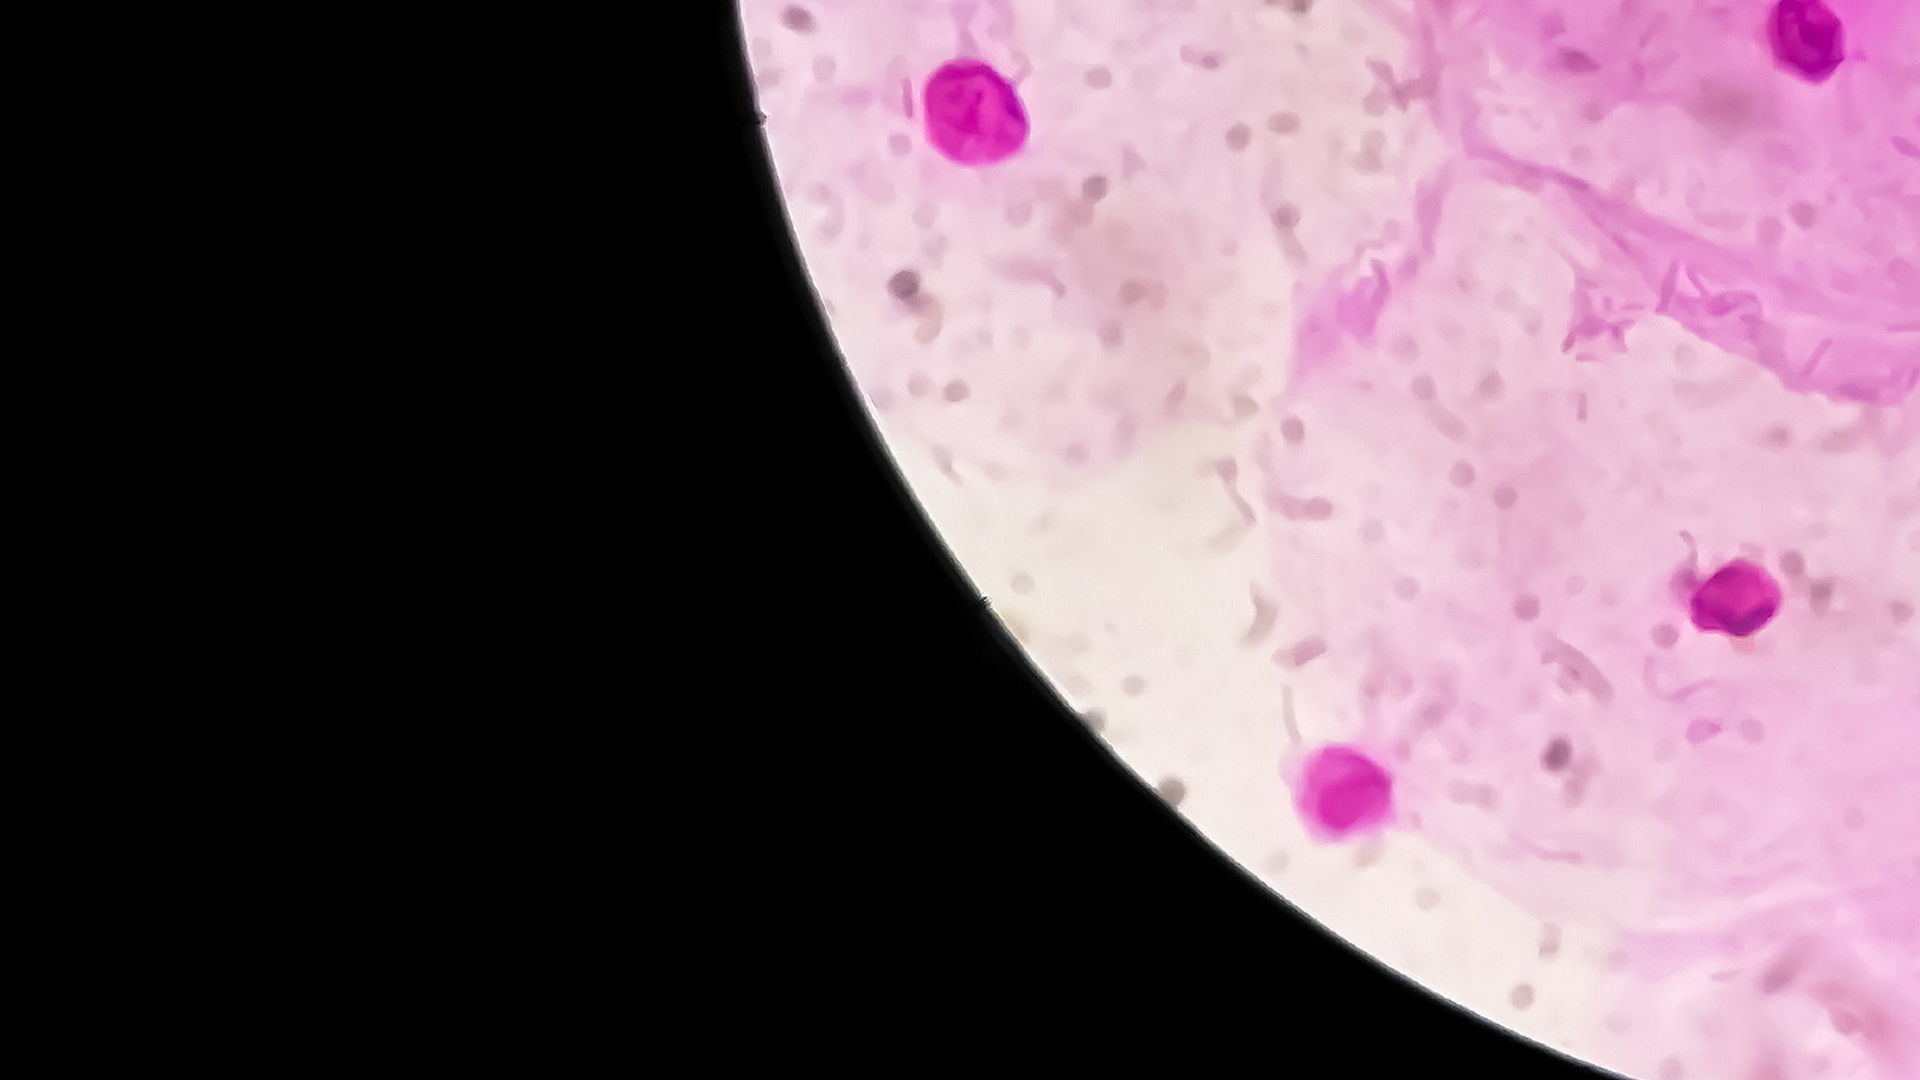

LBC is typically performed in a medical practice for clinician-collected samples when HPV is detected. A sample of cells is collected from the cervix into the liquid-based specimen vial known as ThinPrep®, which is sent to Clinical Labs for analysis to identify the presence of HPV viral DNA at the molecular level.